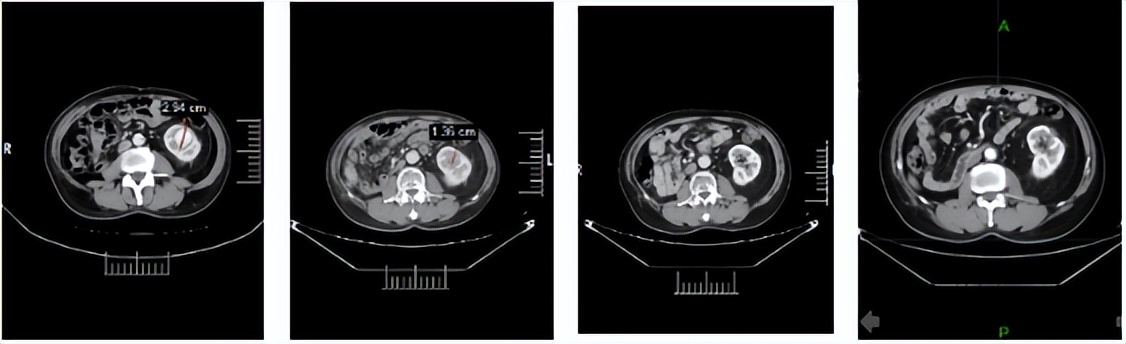

2024年1月3日:治疗4个月后,首次达到PR。

2024年5月9日,决定永久停用信迪利单抗,下调一个剂量水平(4mg,po,qd,D1-14,q3w)恢复呋喹替尼治疗。自此,截至2026年3月30日,呋喹替尼单药治疗约2年且仍在维持中。2026年3月12日行最近一次疗效评估仍处于PR,PFS已达30.4个月。

靶病灶T01:左肾下极

靶病灶T02:左肾上极

靶病灶T03:左侧肾上腺

靶病灶T04:左侧竖脊肌